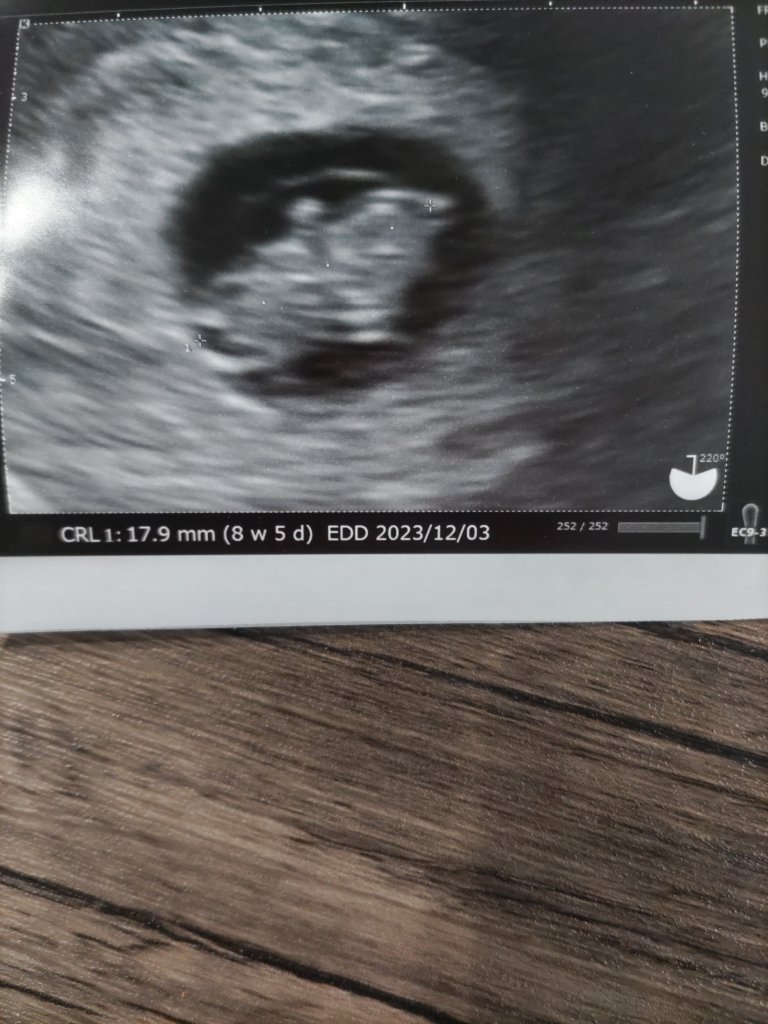

約9週目になりますね、身長約2センチ😃